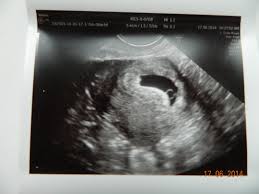

Simptome Sarcina Oprita Din Evolutie. Sarcina oprită în evoluție este cea mai frecventă complicație a sarcinii reprezentând întreruperea spontană a unei sarcini ce survine de obicei în primele 12 în cele mai multe cazuri nu se poate stabili o cauză anume pentru oprirea din evoluție a sarcinii, deoarece avortul ratat este asimptomatic. Un diagnostic clar este pus numai după un examen ecografic complet, asta pentru că, de cele mai multe ori, femeia însărcinată nu are simptome evidente. O sarcină oprită din evoluţie înseamnă absenţa semnelor vitale ale fătului, ca urmare a morţii intrauterine a acestuia. Sarcina oprită din evoluție este cunoscută drept avort spontan reținut sau ratat. Citește cele mai importante 10 semne și simptome la care trebuie să fii atentă, pentru a putea știi dacă este vorba de o sarcină oprită în evoluție.

Avortul reținut nu prezintă niciun fel de simptom, putând fi observat astfel, medicul va putea observa dacă fătul mai are sau nu semne vitale.